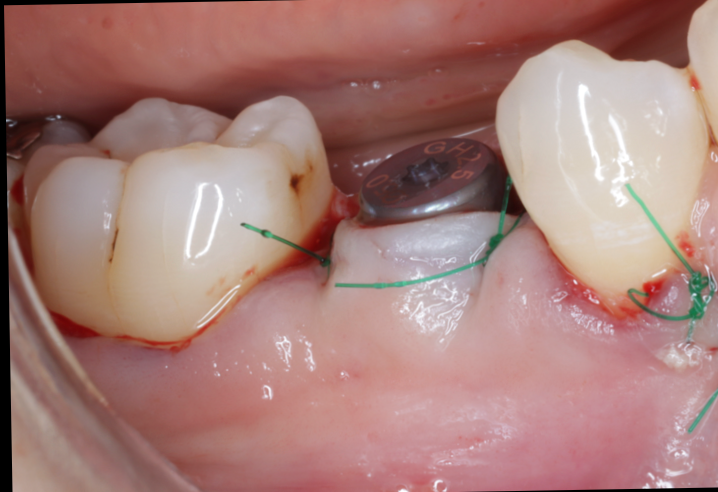

実際の症例紹介

50代女性:

上顎前歯部のインプラント

美容院にお勤めのこの女性は、見た目の問題から仮歯なしでの生活が難しいと判断されていました。

他院では「半年の待機が必要」と診断されたものの、当院では骨の状態と噛み合わせを精密に評価。 BLX+サージカルガイドを使用することで、埋入当日に仮歯の装着を実現しました。 見た目・機能性の両立を求める方にも安心していただける結果となりました。